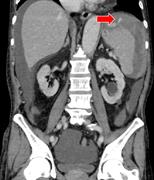

Extensive portal venous gas in a post-operative patient with no identifiable cause

Adam Hussein and Rohit Makhija

Journal of Surgical Case Reports, Volume 2015, Issue 10, October 2015, rjv136, https://doi.org/10.1093/jscr/rjv136